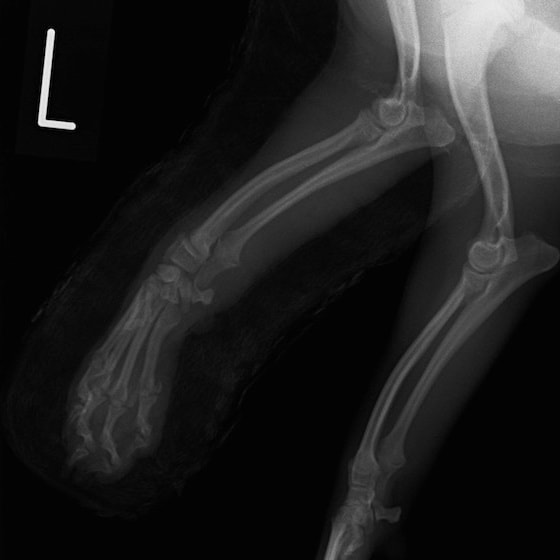

症例:交通事故による椎体脱臼

柴犬:9歳、避妊雌

交通事故直後、胸腰部に激しい疼痛、両後肢に完全麻痺を認め、シェフシェリントン徴候を呈していました。レントゲン検査において、第11-12胸椎間の脱臼が認められました。

脊髄の減圧、脊柱管の再構築・安定化を目的に、片側椎弓切除術およびMatrixMANDIBLE Plateによる椎体固定を実施しました。

隣接椎体を架橋するようにプレートを設置しました。

術後レントゲン写真